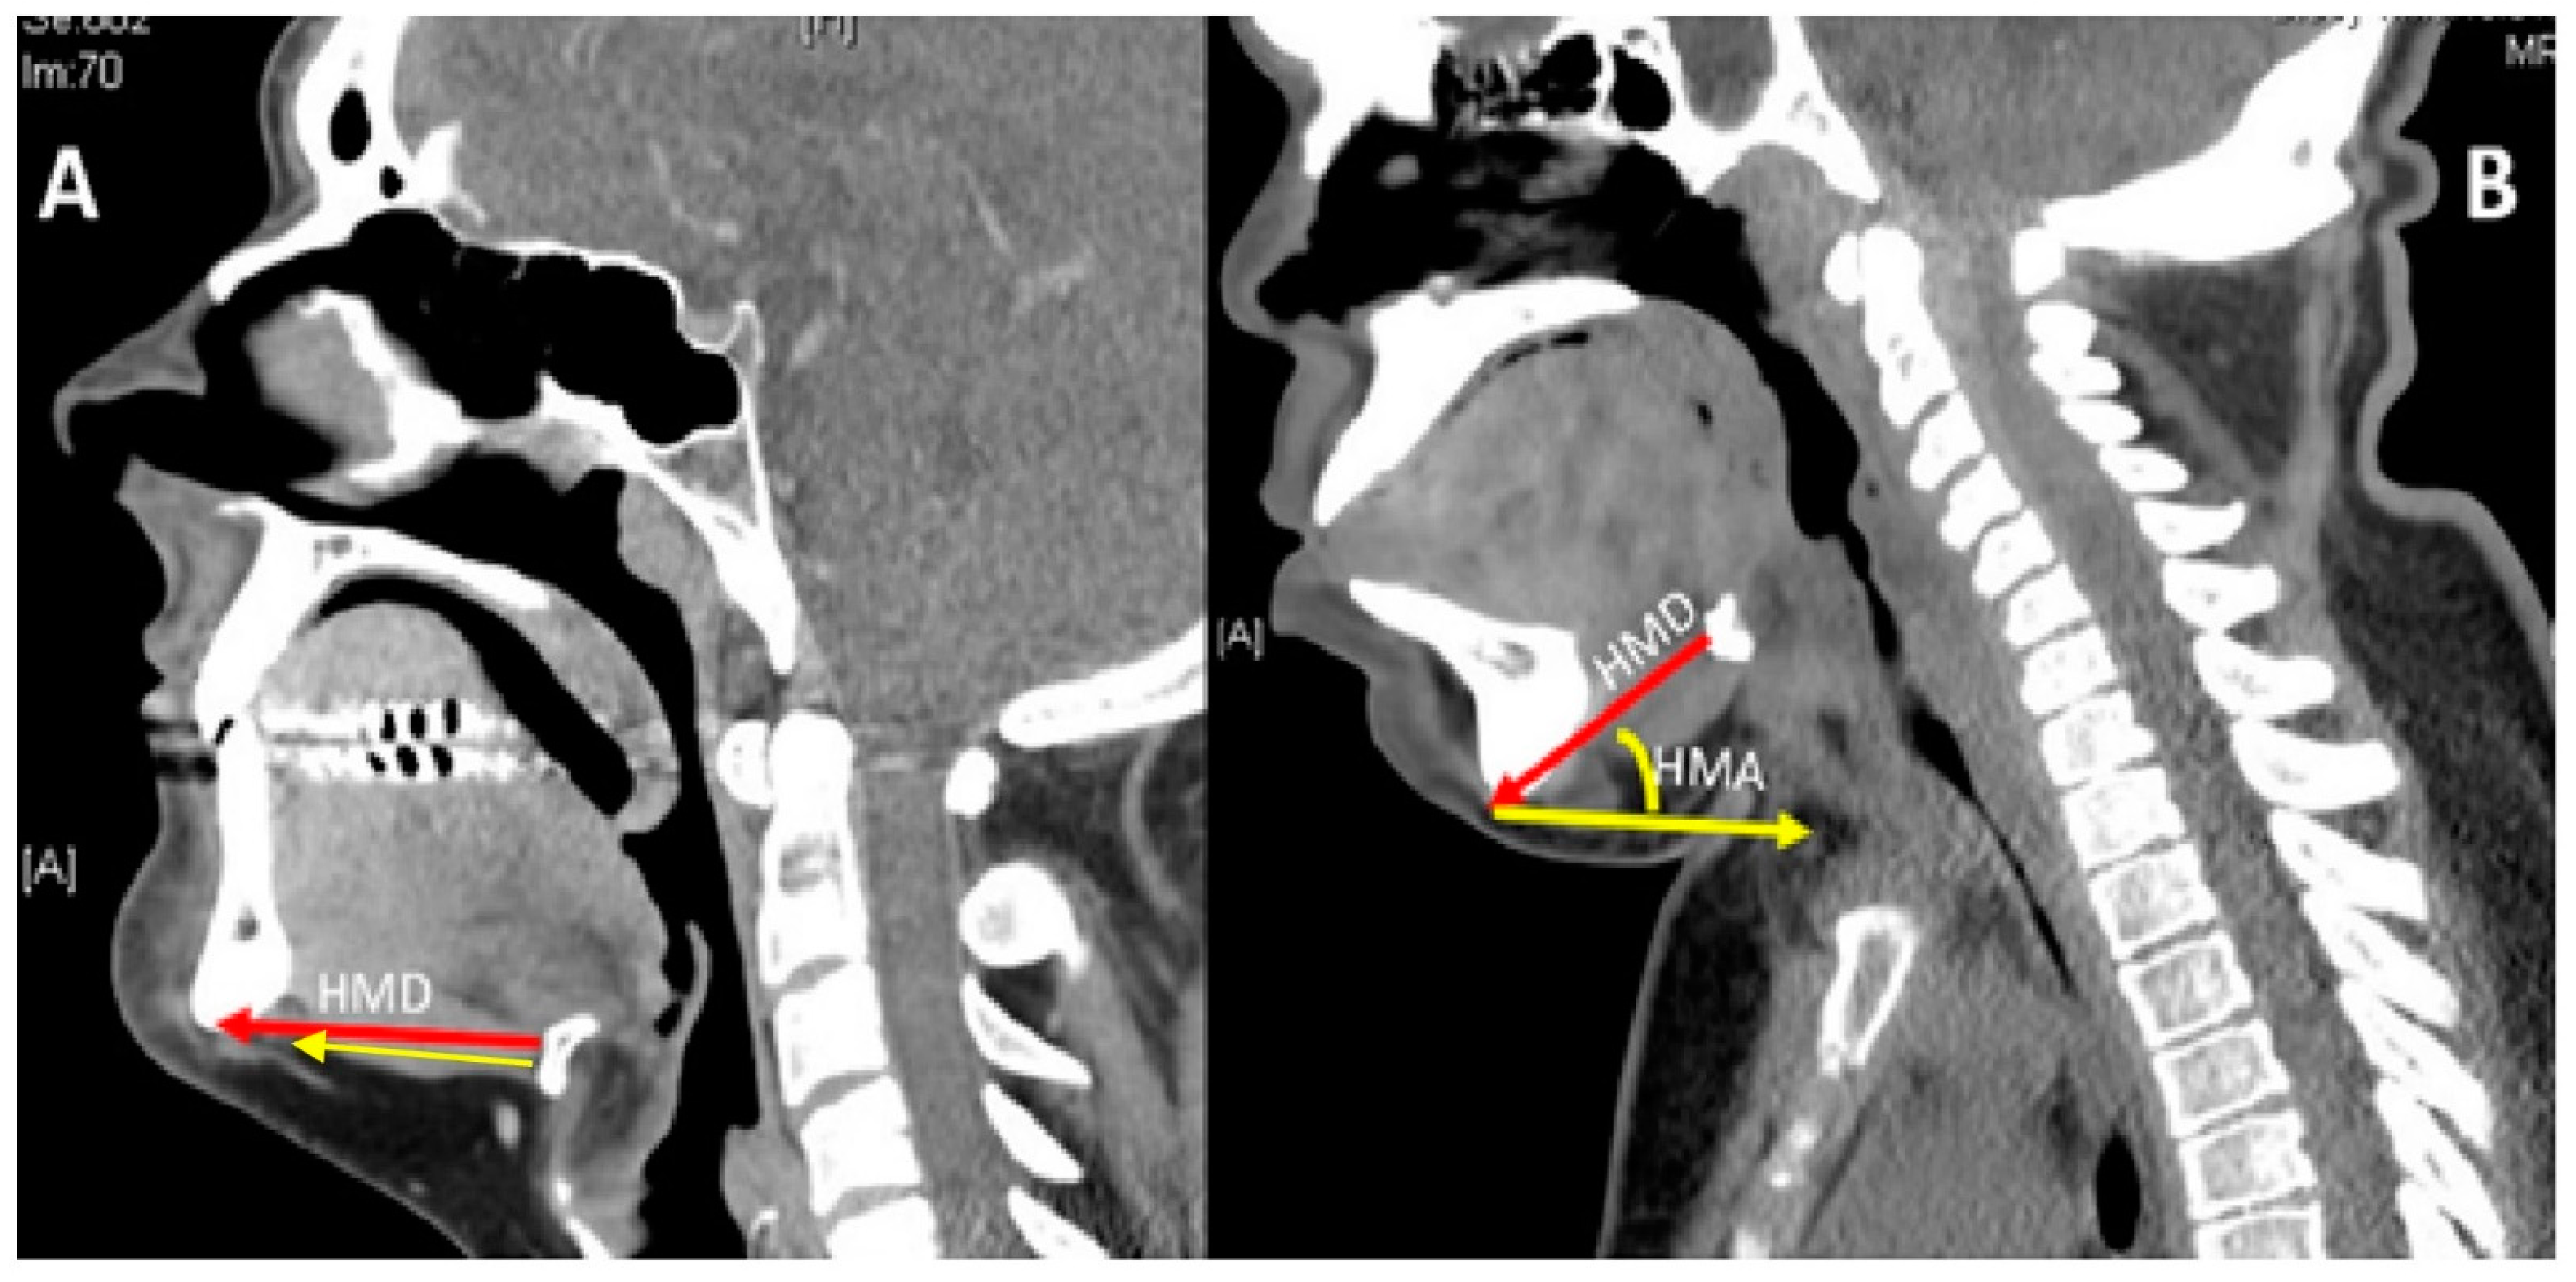

- Sharma, R.; Tol, G.; Stepien, K.; Yadthore, S.; Watson, S.; Samraj, P.; Gadepalli, C. Role of 3-dimensional (3D) reconstruction of radiology images and virtual endoscopy in the assessment of airways in adult mucopolysaccharidosis patients. Mol. Genet. Metab. 2020, 129, S147–S148. [Google Scholar] [CrossRef]

- Han, Y.; Tian, Y.; Zhang, H.; Zhao, Y.; Xu, M.; Guo, X. Radiologic indicators for prediction of difficult laryngoscopy in patients with cervical spondylosis. Acta Anaesthesiol. Scand. 2018, 62, 474–482. [Google Scholar] [CrossRef] [PubMed]